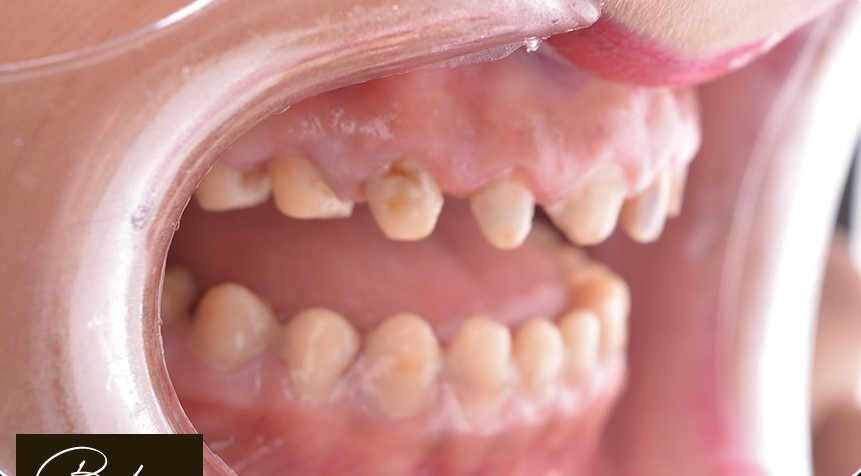

د. حنان ابو الحسن ، مؤسسة Lavender Aesthetic Clinics، هي طبيبة أسنان متخصصة في تركيبات الاسنان ,زراعة الاسنان , حشو عصب ,حشو تجميلي

تميزت برؤيتها اللي بتركز على الجمع بين العلاج الدقيق واللمسة التجميلية، عشان تقدم للمرضى تجربة علاجية مختلفة تجمع بين الصحة، الراحة، والجمال.